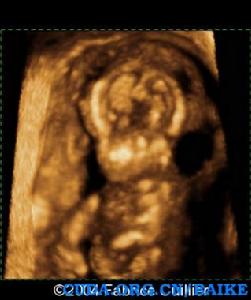

超聲發現:囊性水囊瘤是嚴重X單體的早孕和中孕期典型的徵象。妊娠晚期,孤立的胸腔積液和廣泛的水腫可以發生。最常見的心臟畸形是主動脈弓縮窄。